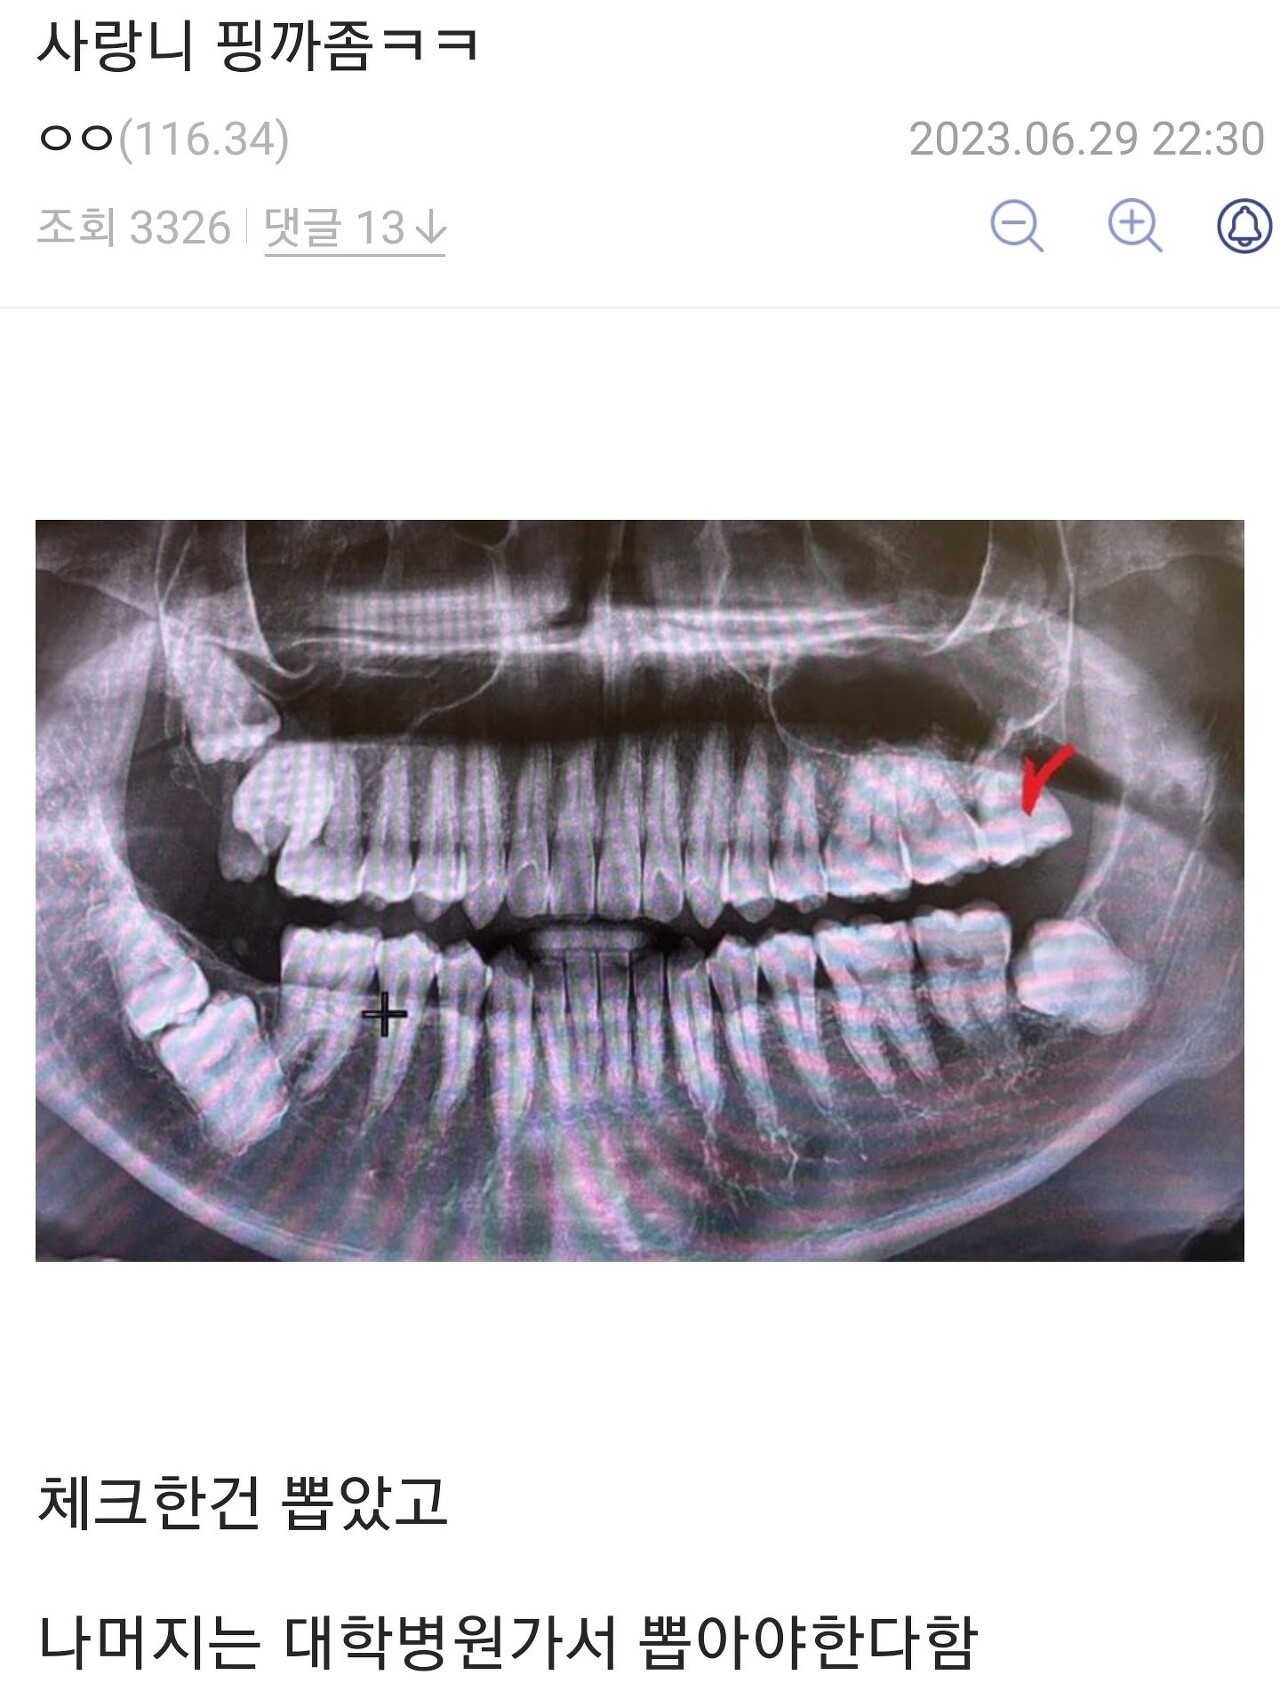

• 작성자설탕안먹어 | 작성시간 24.02.14 밑에서 두번째 사랑니랑 눈 마주침;;

왜 사랑니가 날 보고 있는 건데;;;;;

• 작성자펭귄처럼살자 | 작성시간 24.02.14 한놈은 내쪽으로 보고있네..

• 작성자우리가 맞다는 대답을 할거외다 | 작성시간 24.02.15 저정도면 이가 노출은 되어있는 건가…? 걍 잇몸 안에 박힌 것처럼 생겼는데